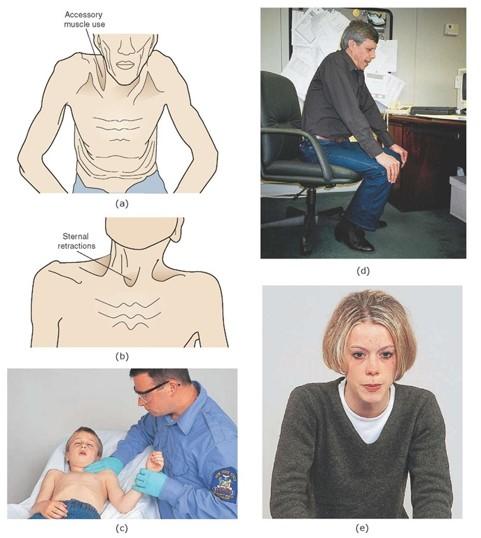

what is one abnormal movement pattern of ventilation? who typically displays this?

name another abnormal ventilation quality? when do you typically see this with?

“Shrug” shoulders...Patients with COPD and other pulmonary disease may display this type of breathing pattern

Asymmetry... see this with trauma/pathology to one lung

- Ex: pneumothorax, etc…